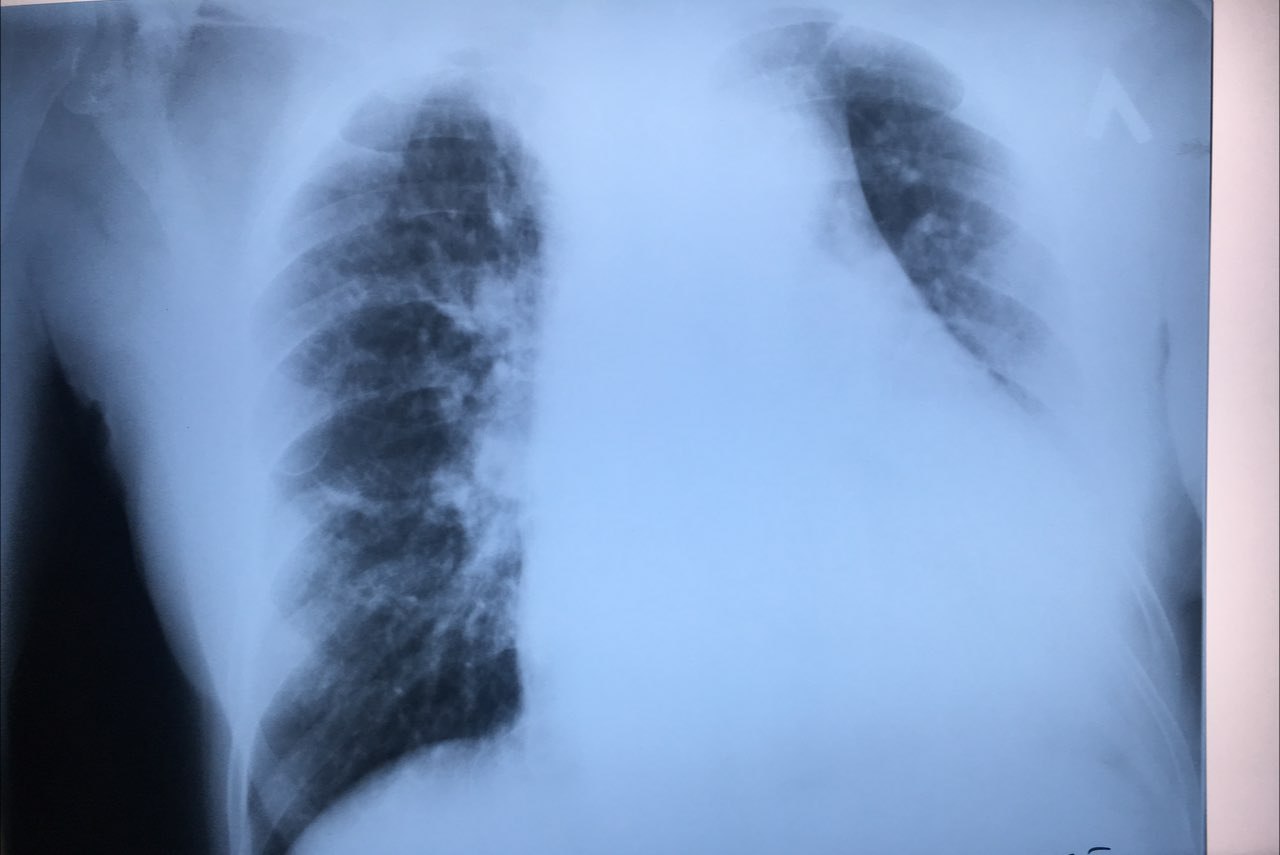

Подскажите,это перелом справа?женщина 1949г.р

Перелом седалищной кости справа?

Доброе утро.Не подскажите,что может быть?